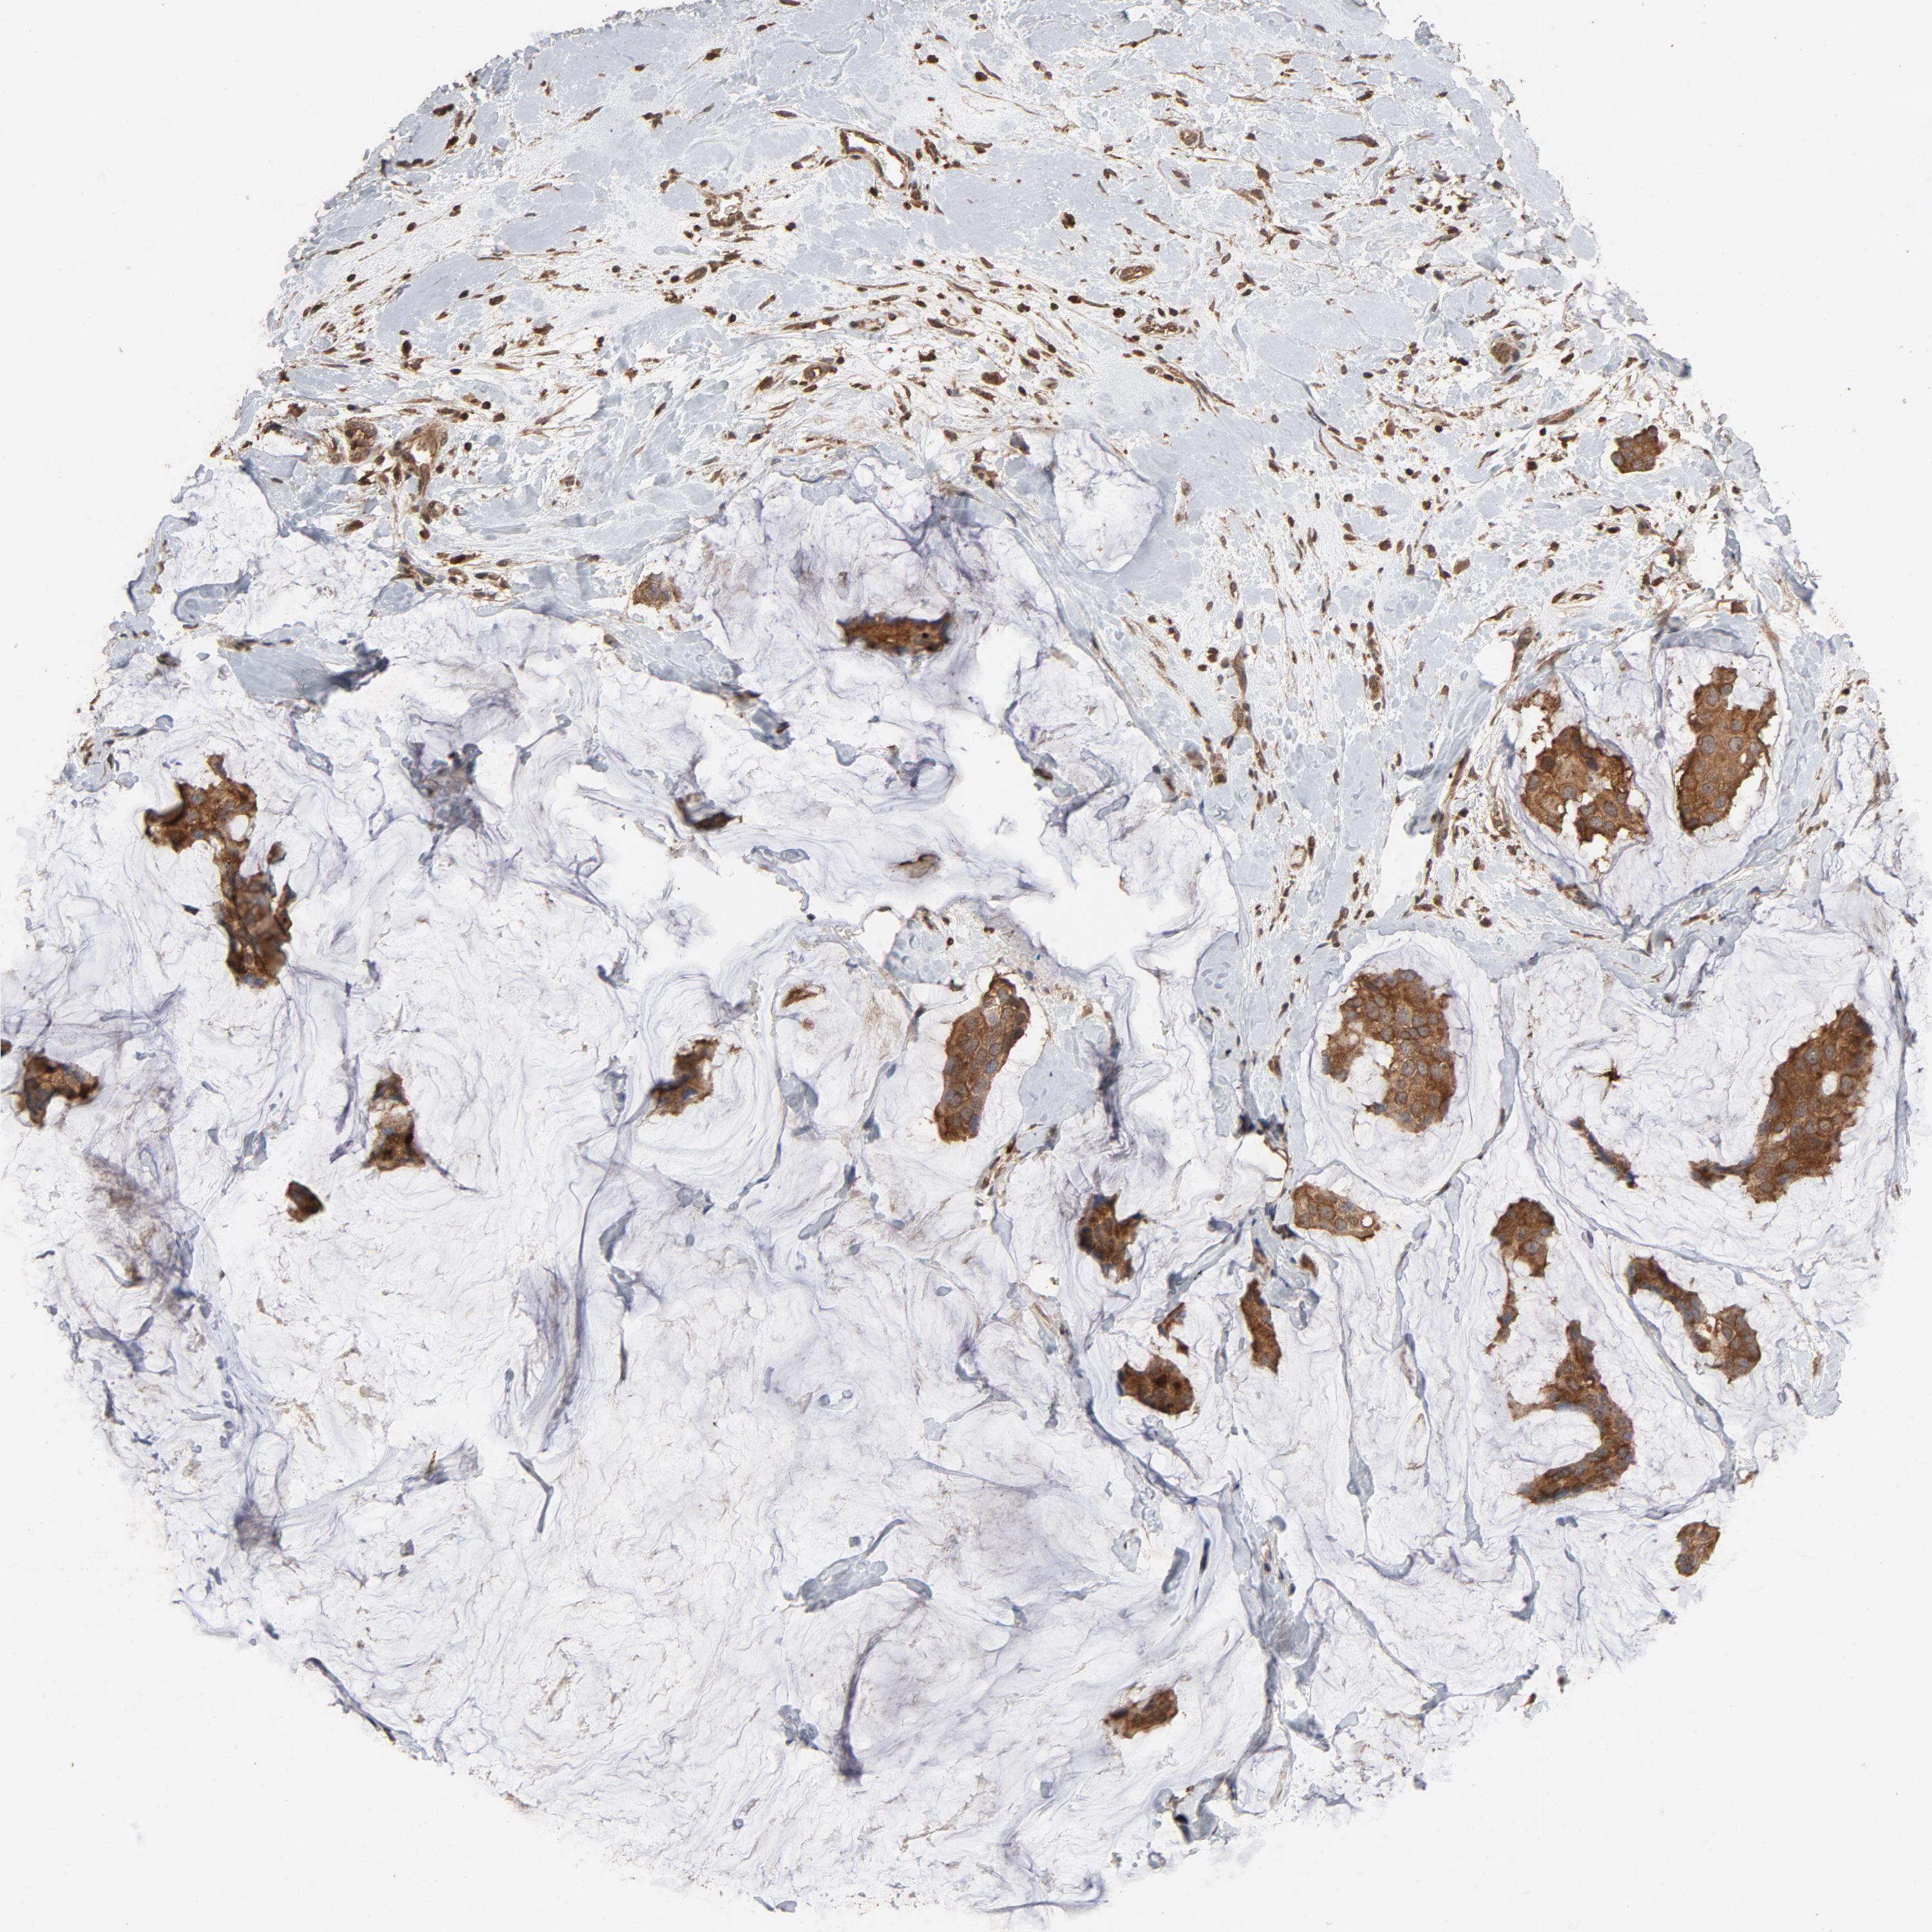

CDC42

CANCER BREAST CANCER Show tissue menu

BRCA TCGA BRCA VALIDATION PROTEIN EXPRESSION